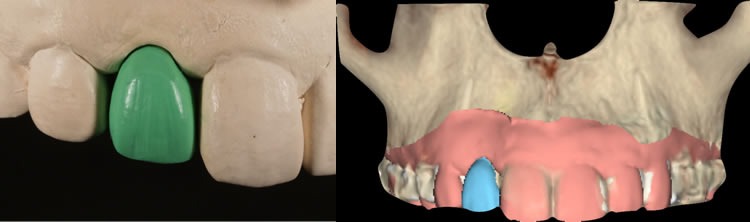

ワックスアップと、Nobel Clinician によるプランニング